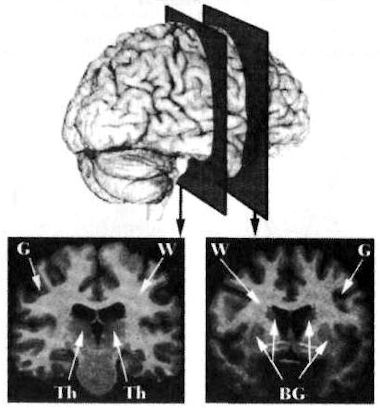

Hanna Damasio aprovechó las ventajas de la neuroanatomía actual y de la tecnología de resonancia magnética nuclear por imágenes.[18] Desarrolló una nueva técnica, que reconstituía tridimensionalmente la imagen del cerebro humano. Llamada «Branvox»,[19]se basa en la manipulación computacional de los cortes cerebrales delineados por el Resonador Magnético Nuclear. En personas vivas, o en pacientes neurológicos, el Resonador entrega una imagen del cerebro que no difiere de la que se puede observar en la mesa de autopsias. Es una fantástica e inquietante maravilla. Piensen lo que Hamlet habría hecho si hubiera podido contemplar un kilo y medio de amenazante e indeciso cerebro, en lugar de la calavera que le ofreció el sepulturero.

Figura 2-2. Cerebro humano vivo, reconstruido en tres dimensiones. La imagen superior muestra el cerebro visto de frente. El cuerpo calloso se esconde debajo de la fisura interhemisférica. Las ilustraciones de la parte inferior, a izquierda y derecha, muestran los dos hemisferios, separados por el medio, como en una operación de cirugía. Las principales estructuras anatómicas están detalladas. La cubierta con voluta es la corteza cerebral.

Cuando consideramos el sistema nervioso en su totalidad, podemos separar fácilmente sus divisiones centrales y periféricas. La reconstrucción tridimensional en la figura 2-2 representa el cerebro, componente principal del sistema nervioso central. Este incluye, además del cerebro o telencéfalo, con sus dos hemisferios, izquierdo y derecho, unidos por el cuerpo calloso (un grueso haz de fibras nerviosas que conecta ambos lados bidireccionalmente), el diencéfalo (un conjunto de núcleos escondido bajo los hemisferios, que incluye el tálamo y el hipotálamo), el cerebro medio o mesencéfalo, el tronco del encéfalo, el cerebelo y la médula espinal.

Figura 2-3. Dos secciones de un cerebro humano viviente, reconstruidas por el Resonador Magnético (MRI), usando la técnica Brainvox. Los planos de sección se identifican en la parte superior de la ilustración. La diferencia entre materia gris (G) y blanca (W) se puede ver fácilmente. La materia gris aparece en la corteza, especie de cinta grisácea que envuelve totalmente cada grieta y circunvolución de la sección, y en los núcleos profundos como los ganglios básales (BG) y el tálamo (Th).

Cuando seccionamos el sistema nervioso central, podemos discernir sin dificultad la diferencia entre sus sectores oscuros y pálidos. (Figura 2-3). Los niveles tintos se conocen como materia gris, pese a que su color es habitualmente más pardo que grisáceo. Los sectores pálidos se conocen como materia decolorada. La mayor parte de la materia gris está conformada por colecciones de cuerpos celulares neurales, en tanto que la materia decolorada se compone de axones, o fibras nerviosas, emanados desde la zona gris.